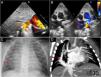

Neonato a término de 10 días, valorado por soplo cardíaco sistólico. La ecocardiografía mostró dilatación de cavidades derechas y una única vena pulmonar derecha ingurgitada drenando a vena cava inferior (fig. 1A), con retorno venoso izquierdo normal (fig. 1B). La radiografía evidenció discreta cardiomegalia y congestión pulmonar leve (fig. 1C). Una angio-tomografía computarizada (angio-TC) confirmó los hallazgos ecocardiográficos, e identificó una colateral aortopulmonar originada en aorta abdominal, aportando flujo hacia lóbulo inferior derecho (figs. 1D y 2A y B). Fue establecido el diagnóstico de síndrome de cimitarra. Durante los 10 primeros meses el lactante presentó polipnea intermitente requiriendo dosis bajas de diurético. A los 11 meses de vida, por dilatación progresiva del ventrículo derecho, se realizó oclusión percutánea del flujo arterial colateral aortopulmonar, implantándose dispositivo Amplatzer® Vascular Plug-II 6mm (figs. 2C y D). Seis meses después, el ventrículo derecho se observó menos dilatado (reducción del valor z-score del diámetro telediastólico de +3,6 a +1,7).

A) Ecocardiografía. Plano subcostal visualizando la vena cimitarra (flecha roja) drenando en la porción final de la vena cava inferior. B) Ecocardiografía. Plano supraesternal, mostrando el drenaje normal de venas pulmonares izquierdas a aurícula izquierda. No se observan venas pulmonares en el lado derecho. C) Radiografía de tórax. Cardiomegalia y leve congestión del pulmón derecho. La flecha roja señala la vena cimitarra. D) Angio-TC. Visión coronal. Se observa el drenaje anómalo del pulmón derecho a través de una única y dominante vena pulmonar (vena cimitarra, flecha roja), a vena cava inferior, pareciendo una espada curva originada en Oriente Medio conocida como cimitarra.

AD: aurícula derecha; AI: aurícula izquierda; VCI: vena cava inferior; VPI: venas pulmonares izquierdas.